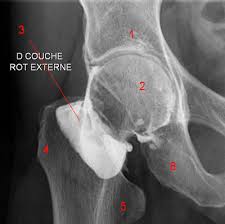

Arthrographie

L'arthrographie est une radiographie avec préparation. La préparation consiste à faire pénétrer un gaz ou une substance opaque aux rayons X dans l'articulation que l'on désire explorer radiologiquement notamment pour détecter des anomalies dans le ménisque. Après l'injection du produit de contraste dans l'articulation, on prend des cliches du genou de face, de profil ou oblique avec plusieurs degrés d'inclinaison .